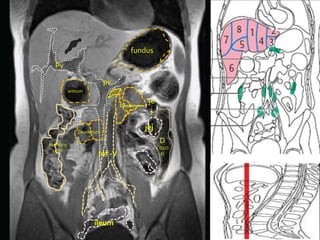

fundus

PV

body     Splenic

GB antrum                F

Hf

SMV

SMA

cecum

ileum            DC

VERMIFORM APPENDIX

antrum

Deodenum

je

j

jej

Asending

D

colon                                          COLO

Inf -V                     N

ileum